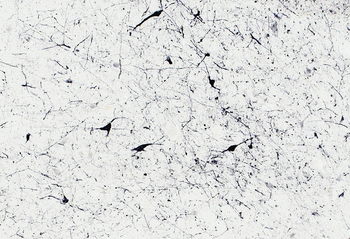

Immunostaining of 30 µm thick cryosections of PFA-perfused Human Hypothalamus, antigen retrieval with citrate buffer Ph 6 at 80C for 30 min, HRP-staining with Ni-DAB after Biotin-SP-antigoat amplification.